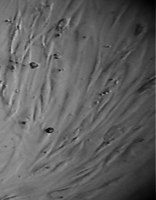

Клетки культивировали в стандартных условиях в термостате Sanyo – Incubator MIR-262 при температуре 37°С в среде МЕМ с 10% эмбриональной телячьей сыворотки в пластиковых культуральных флаконах Orange Scientific (производство Бельгии), Corning (производство США) площадью 25 и 75 кв. см. Тестирование производили в культуральных чашках Петри Sarstedt диаметром 3 см (рис. 3).

Вид монослоя и структура клеток не отличались от обычных в течение всех четырех суток наблюдения (рис. 32).

На всей остальной поверхности дна опытной чашки монослой был целостным и равномерным, фибробласты сохраняли обычную структуру, форму и размеры.

Вид монослоя и структура клеток не отличались от обычных в течение всех четырех суток наблюдения.